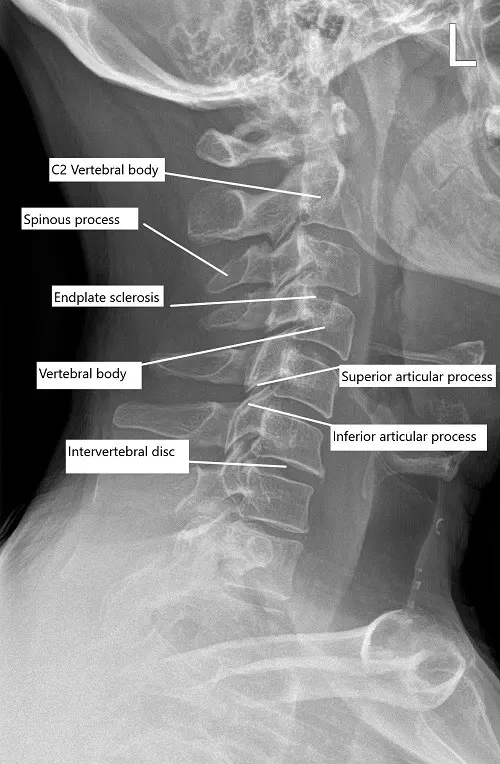

Pre-operative x-ray of the cervical spine in lateral view